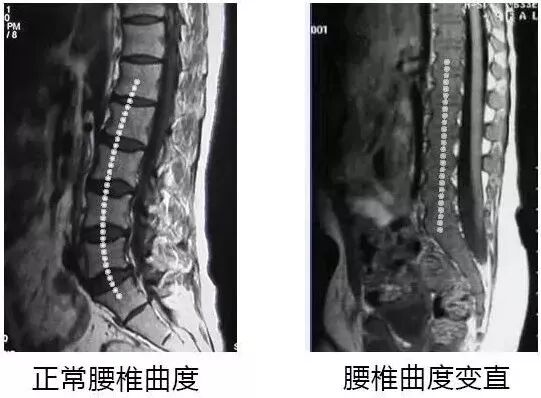

这种姿势让脊椎一直维持着“弓背”的状态

全身的重量全压在脊椎骨底端

一旦腰椎受到挤压,整个身体就变形了

腰椎间盘变直,反弓